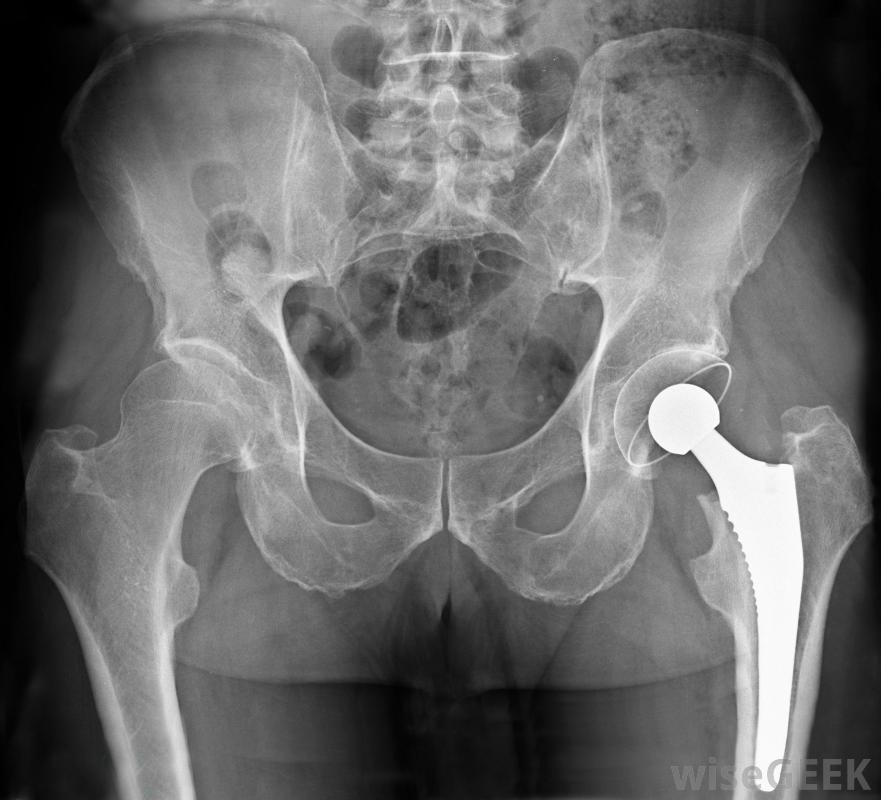

严重的髋关节压力骨折可能需要髋关节置换手术来修复。除了处理髋部应力性骨折带来的疼痛外,你的医生也可能要求你戴上某种保护性绷带,帮助固定臀部这是为了减轻髋部骨折的部分压力,使你身体的自然愈合过程更容易开始修复损伤。除了包裹髋关节外,你的医生也很有可能建议在髋部愈合时使用拐杖或助行器

治疗髋部应力性骨折可能需要物理治疗。根据髋部应力性骨折的严重程度,可能需要手术来促进愈合过程。如果应力性骨折是某种物理创伤(如意外事故)的结果,尤其如此。手术可以让医护人员直观地评估损伤情况,帮助恢复碎片的排列,如果损伤特别严重,可能需要进行髋关节置换手术。